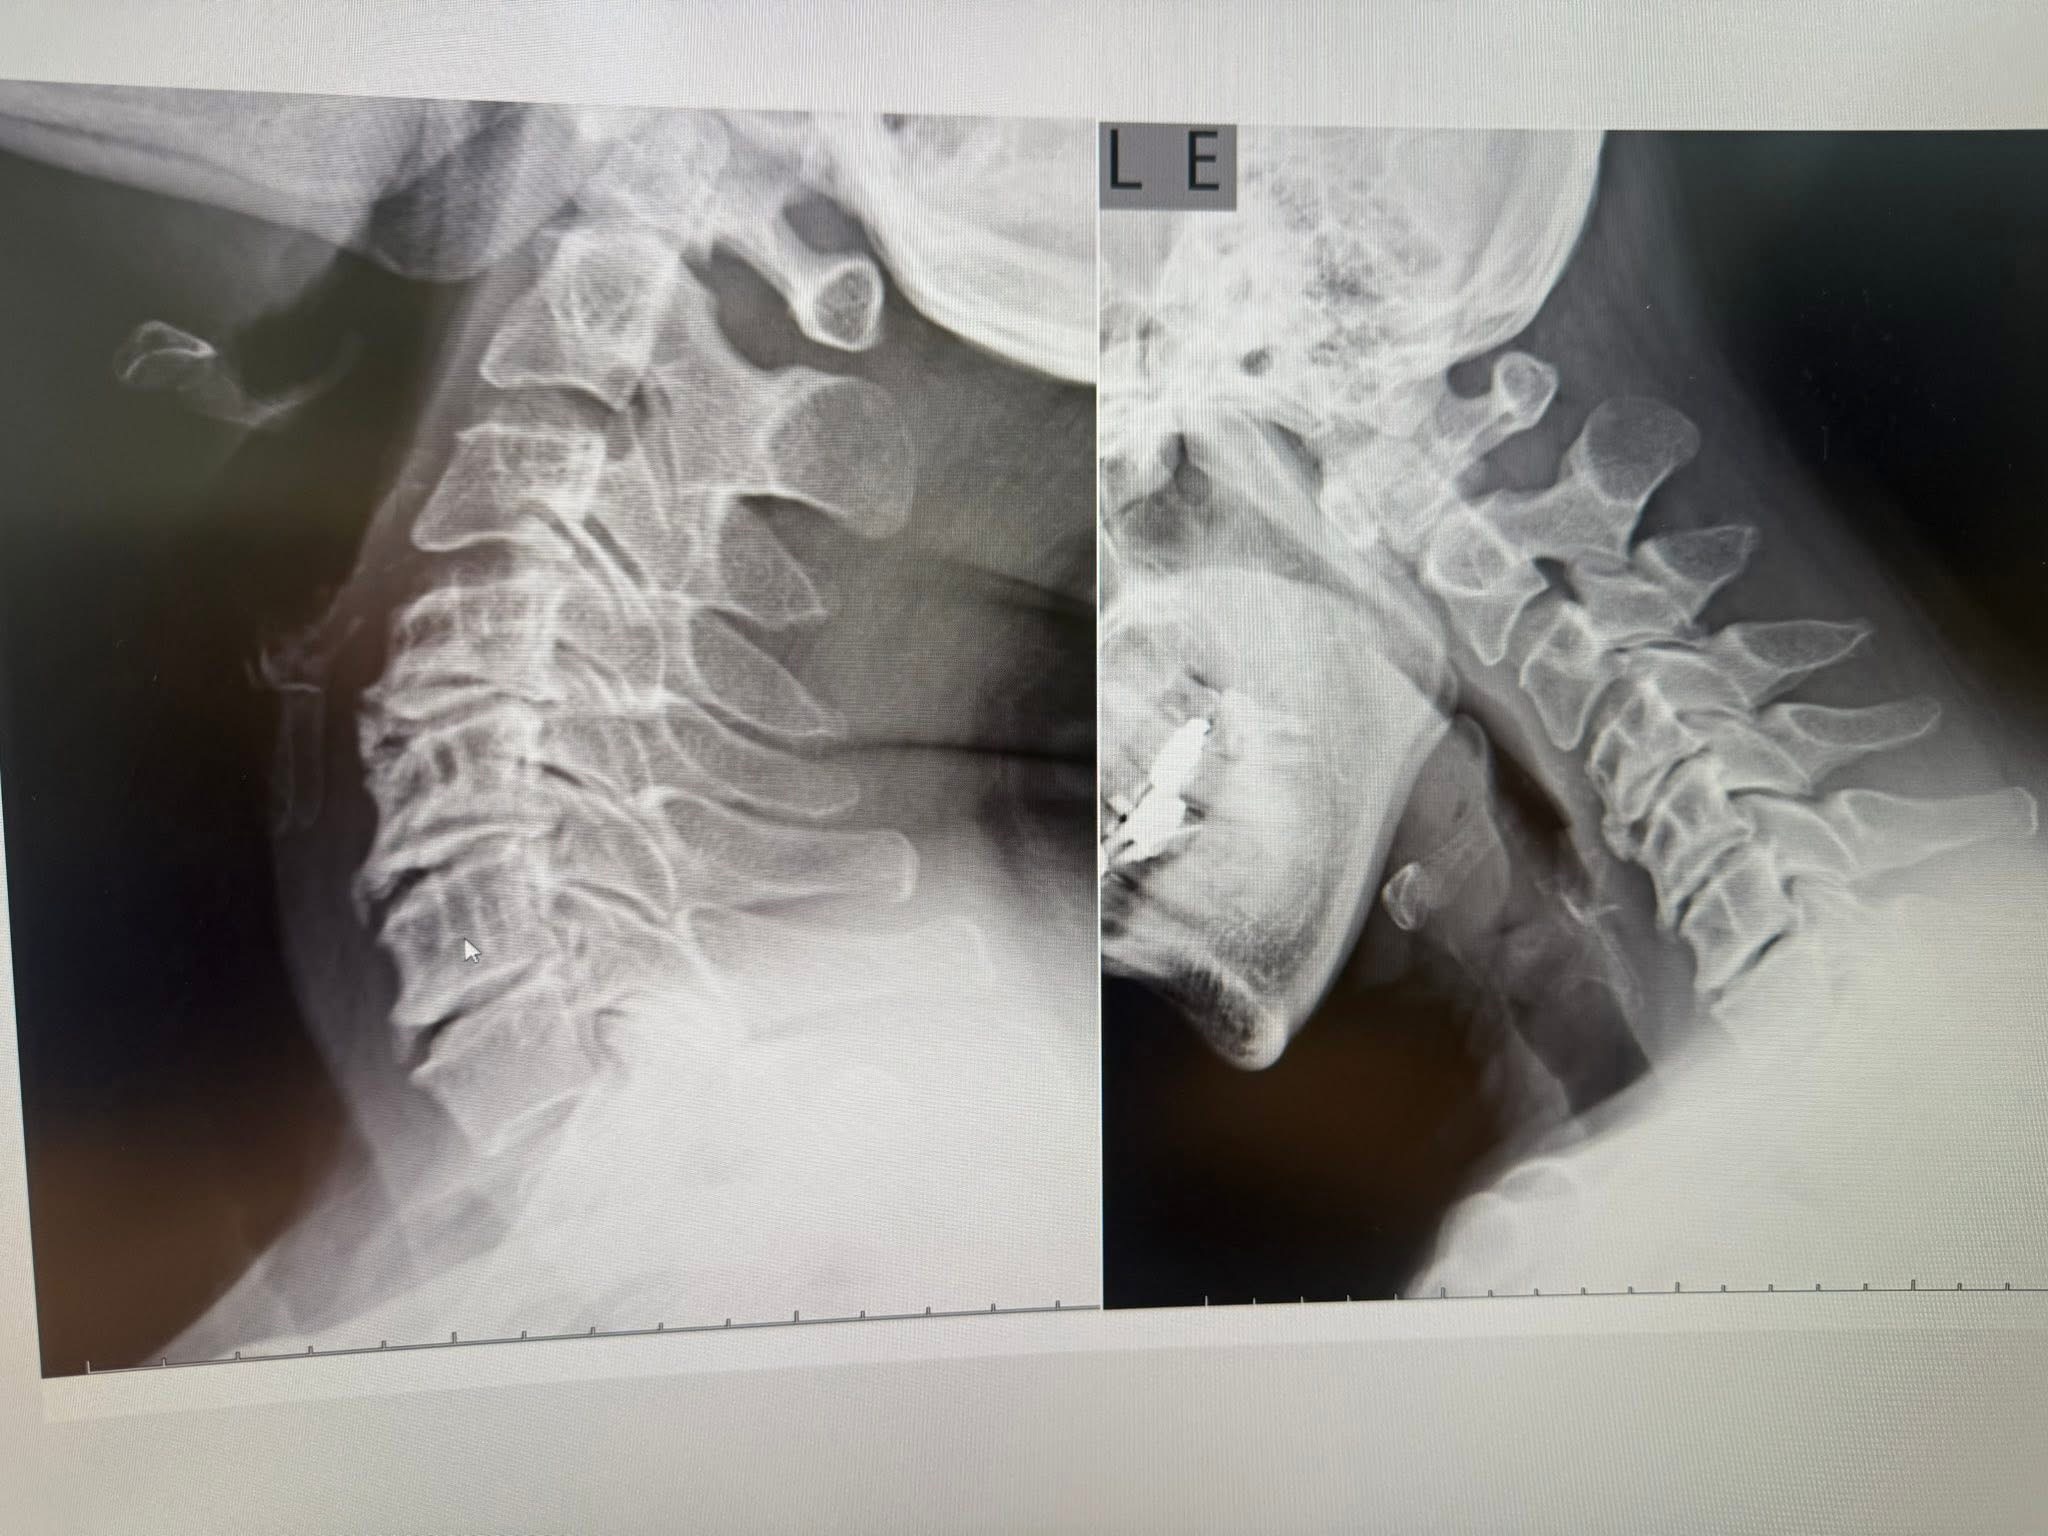

頸椎X光與MRI,真相很明確:

• X光顯示頸椎生理弧度變直,C5–C6不穩,前彎活動受限

• MRI則清楚看見C4/5、C5/6、C6/C三節都椎間盤突出,C5/6明顯壓迫脊髓與左側神經根